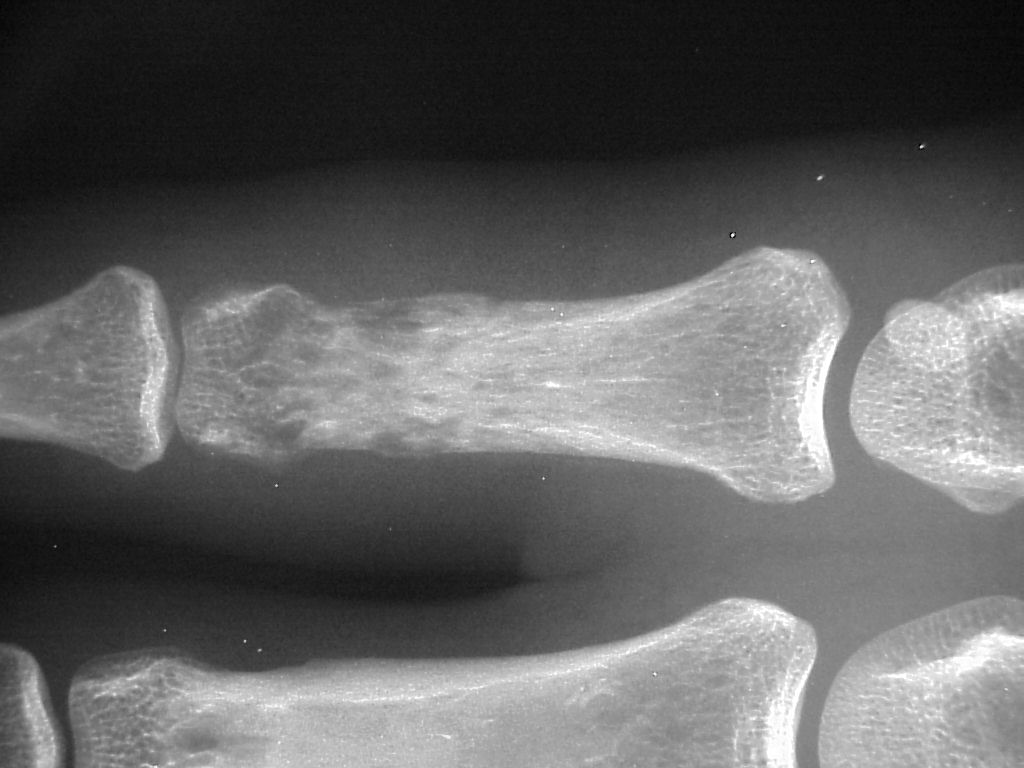

Radiographic erosive changes of the proximal phalanx.